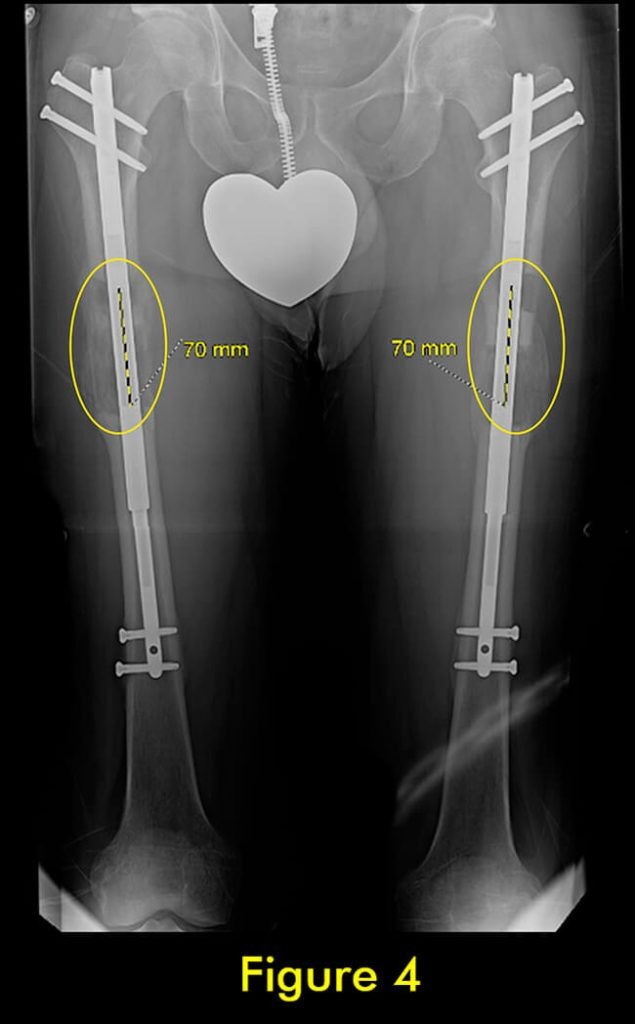

过早合并示意图4

图4:完全巩固